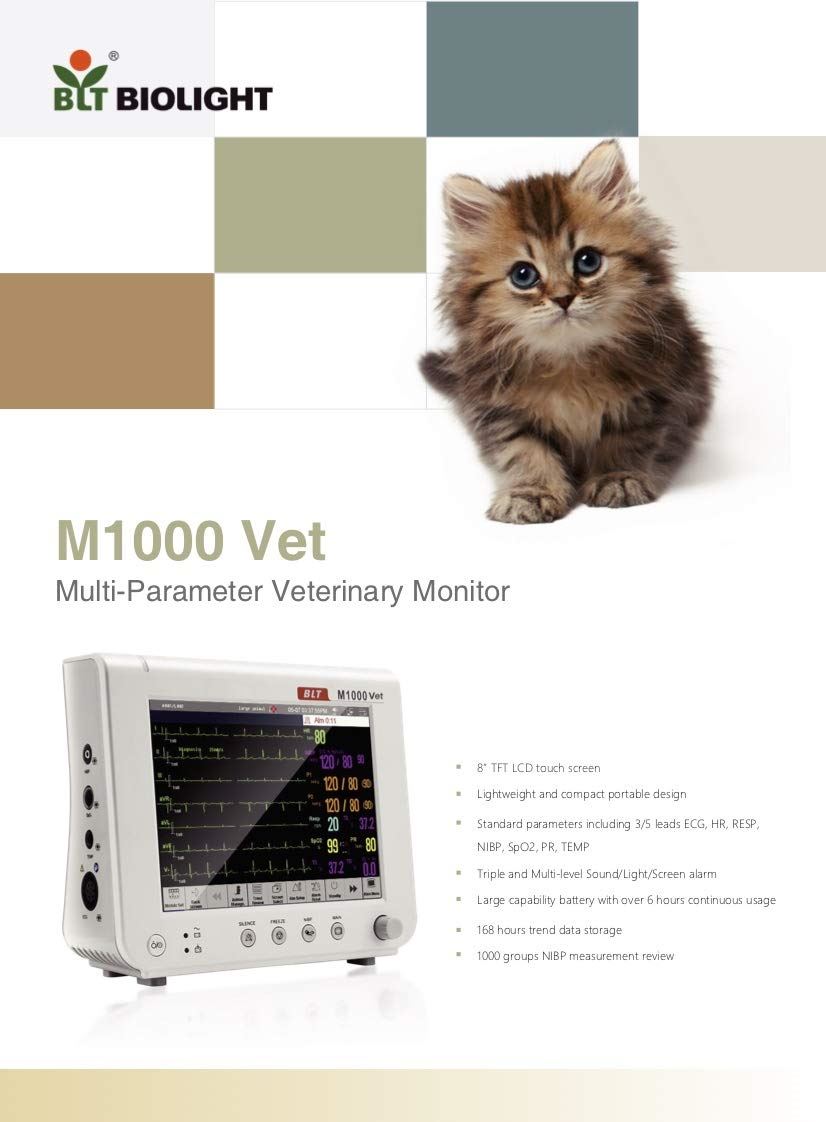

BLT M1000Vet Veterinary Multi Parameter Monitors

Sale price$ 2,089.60